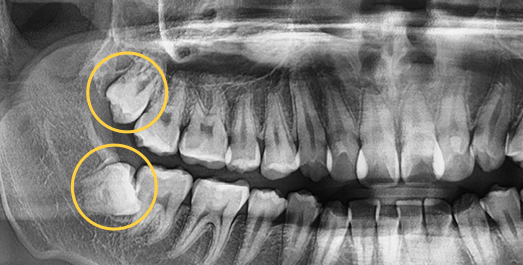

• 수평으로

숨어있는 사랑니

• 각도를 가지고

• BEFORE

• AFTER

치료기간 : 2024.09.04